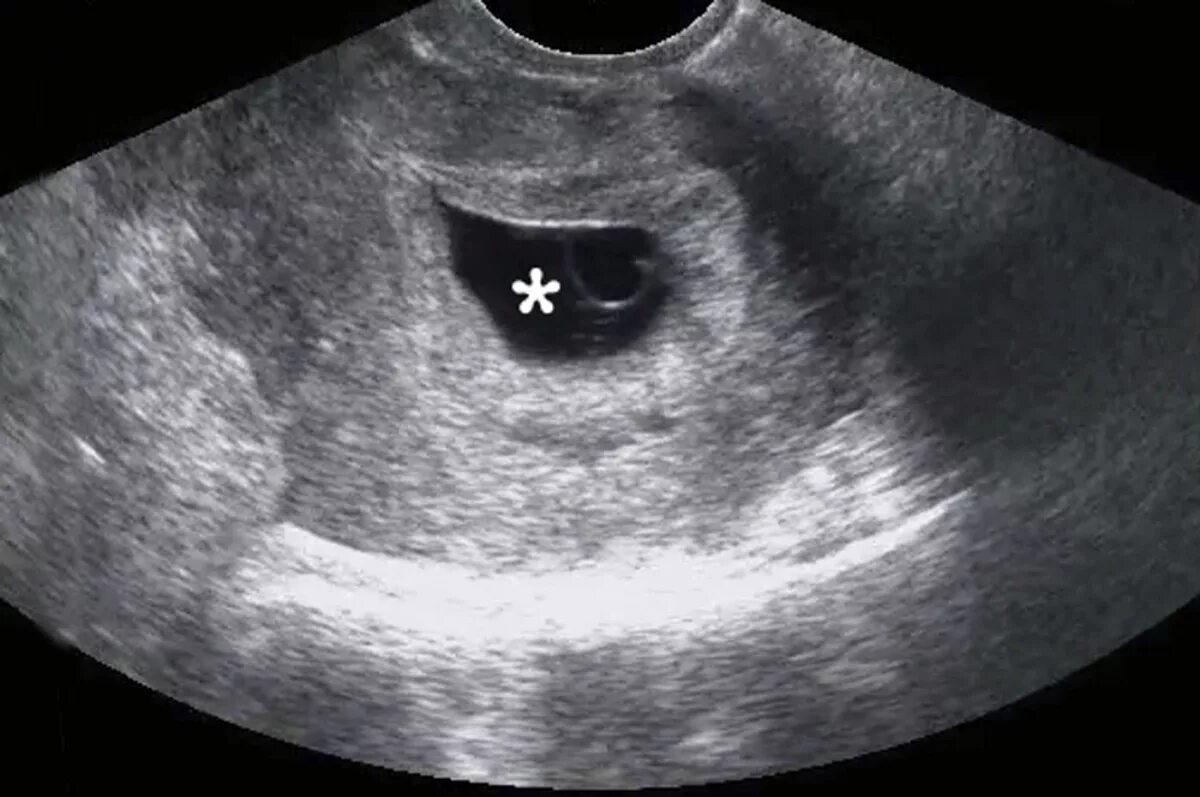

7 неделя февраля